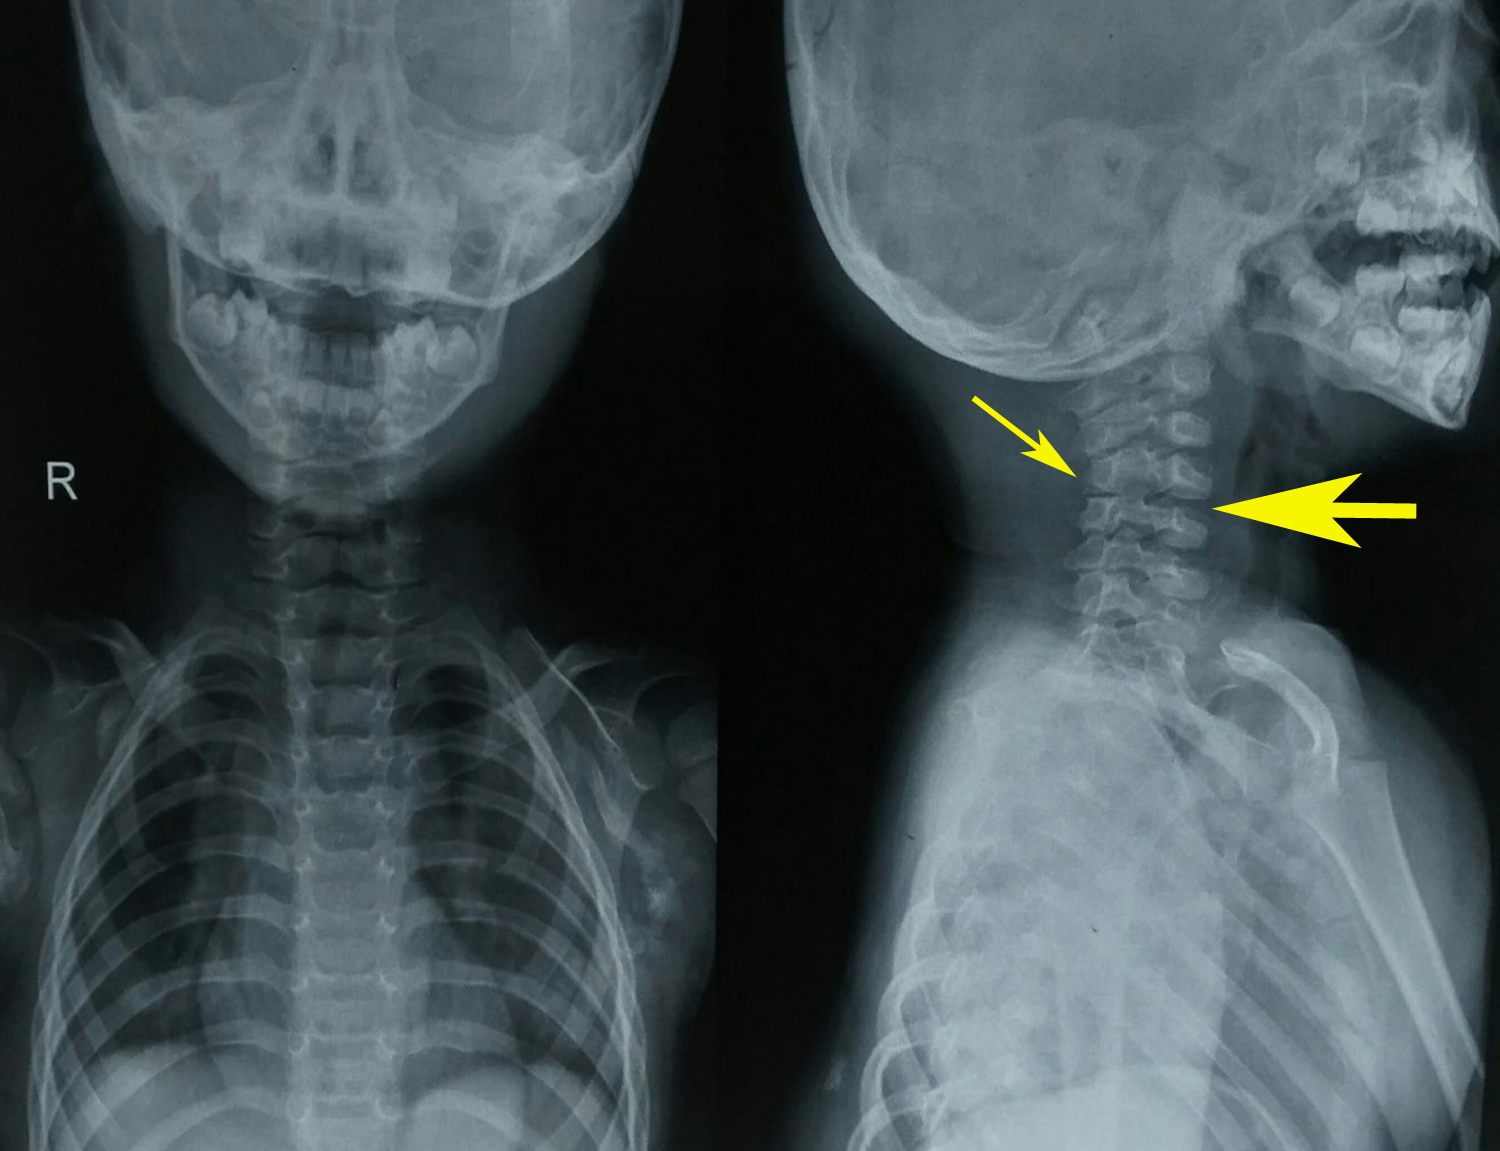

Physical examination revealed bilateral shortening and valgus deformity of the great toes (Figure 1). Multiple swellings of variable size were present on occiput, nape of neck, bilateral scapular area, bilateral axilla and midback. Swellings were non tender, hard, smooth, mobile with well-defined edges and were lying in subcutaneous tissues & muscles. Movements of the neck and bilateral shoulder were decreased (Figure 3). Rest of the joints including bilateral hips, elbows, wrists, knee, and ankle were normal. A radiograph of the right shoulder showed osteomas between the scapula and the proximal end of the humerus (Figure 4). Cervical spine radiographs revealed large posterior elements, narrow vertebral bodies and loss of cervical lordosis (Figure 5). Radiograph of the dorso-lumbar spine revealed large ectopic bone mass bridging the lower dorsal and lumbar spine (Figure 6). Radiograph of the knees revealed the presence of osteochondromas of the proximal medial end of the tibia (Figure 7). Lab findings were normal except for raised ESR (50mm in first hour) & liver enzymes were mildly raised. Patient was diagnosed as a case of FOP on the basis of clinico-radiological examinations. Biopsy was not done because of the fear of flaring up of the disease. Oral prednisolone was given in a dose of 2mg/kg for 5 days. Acute flare of the disease settled and the patient was discharged with advice of regular follow-ups.

Figure 5 Cervical spine radiograph revealed large posterior elements (thin arrow), narrow vertebral bodies and loss of cervical lordosis (thick arrow).